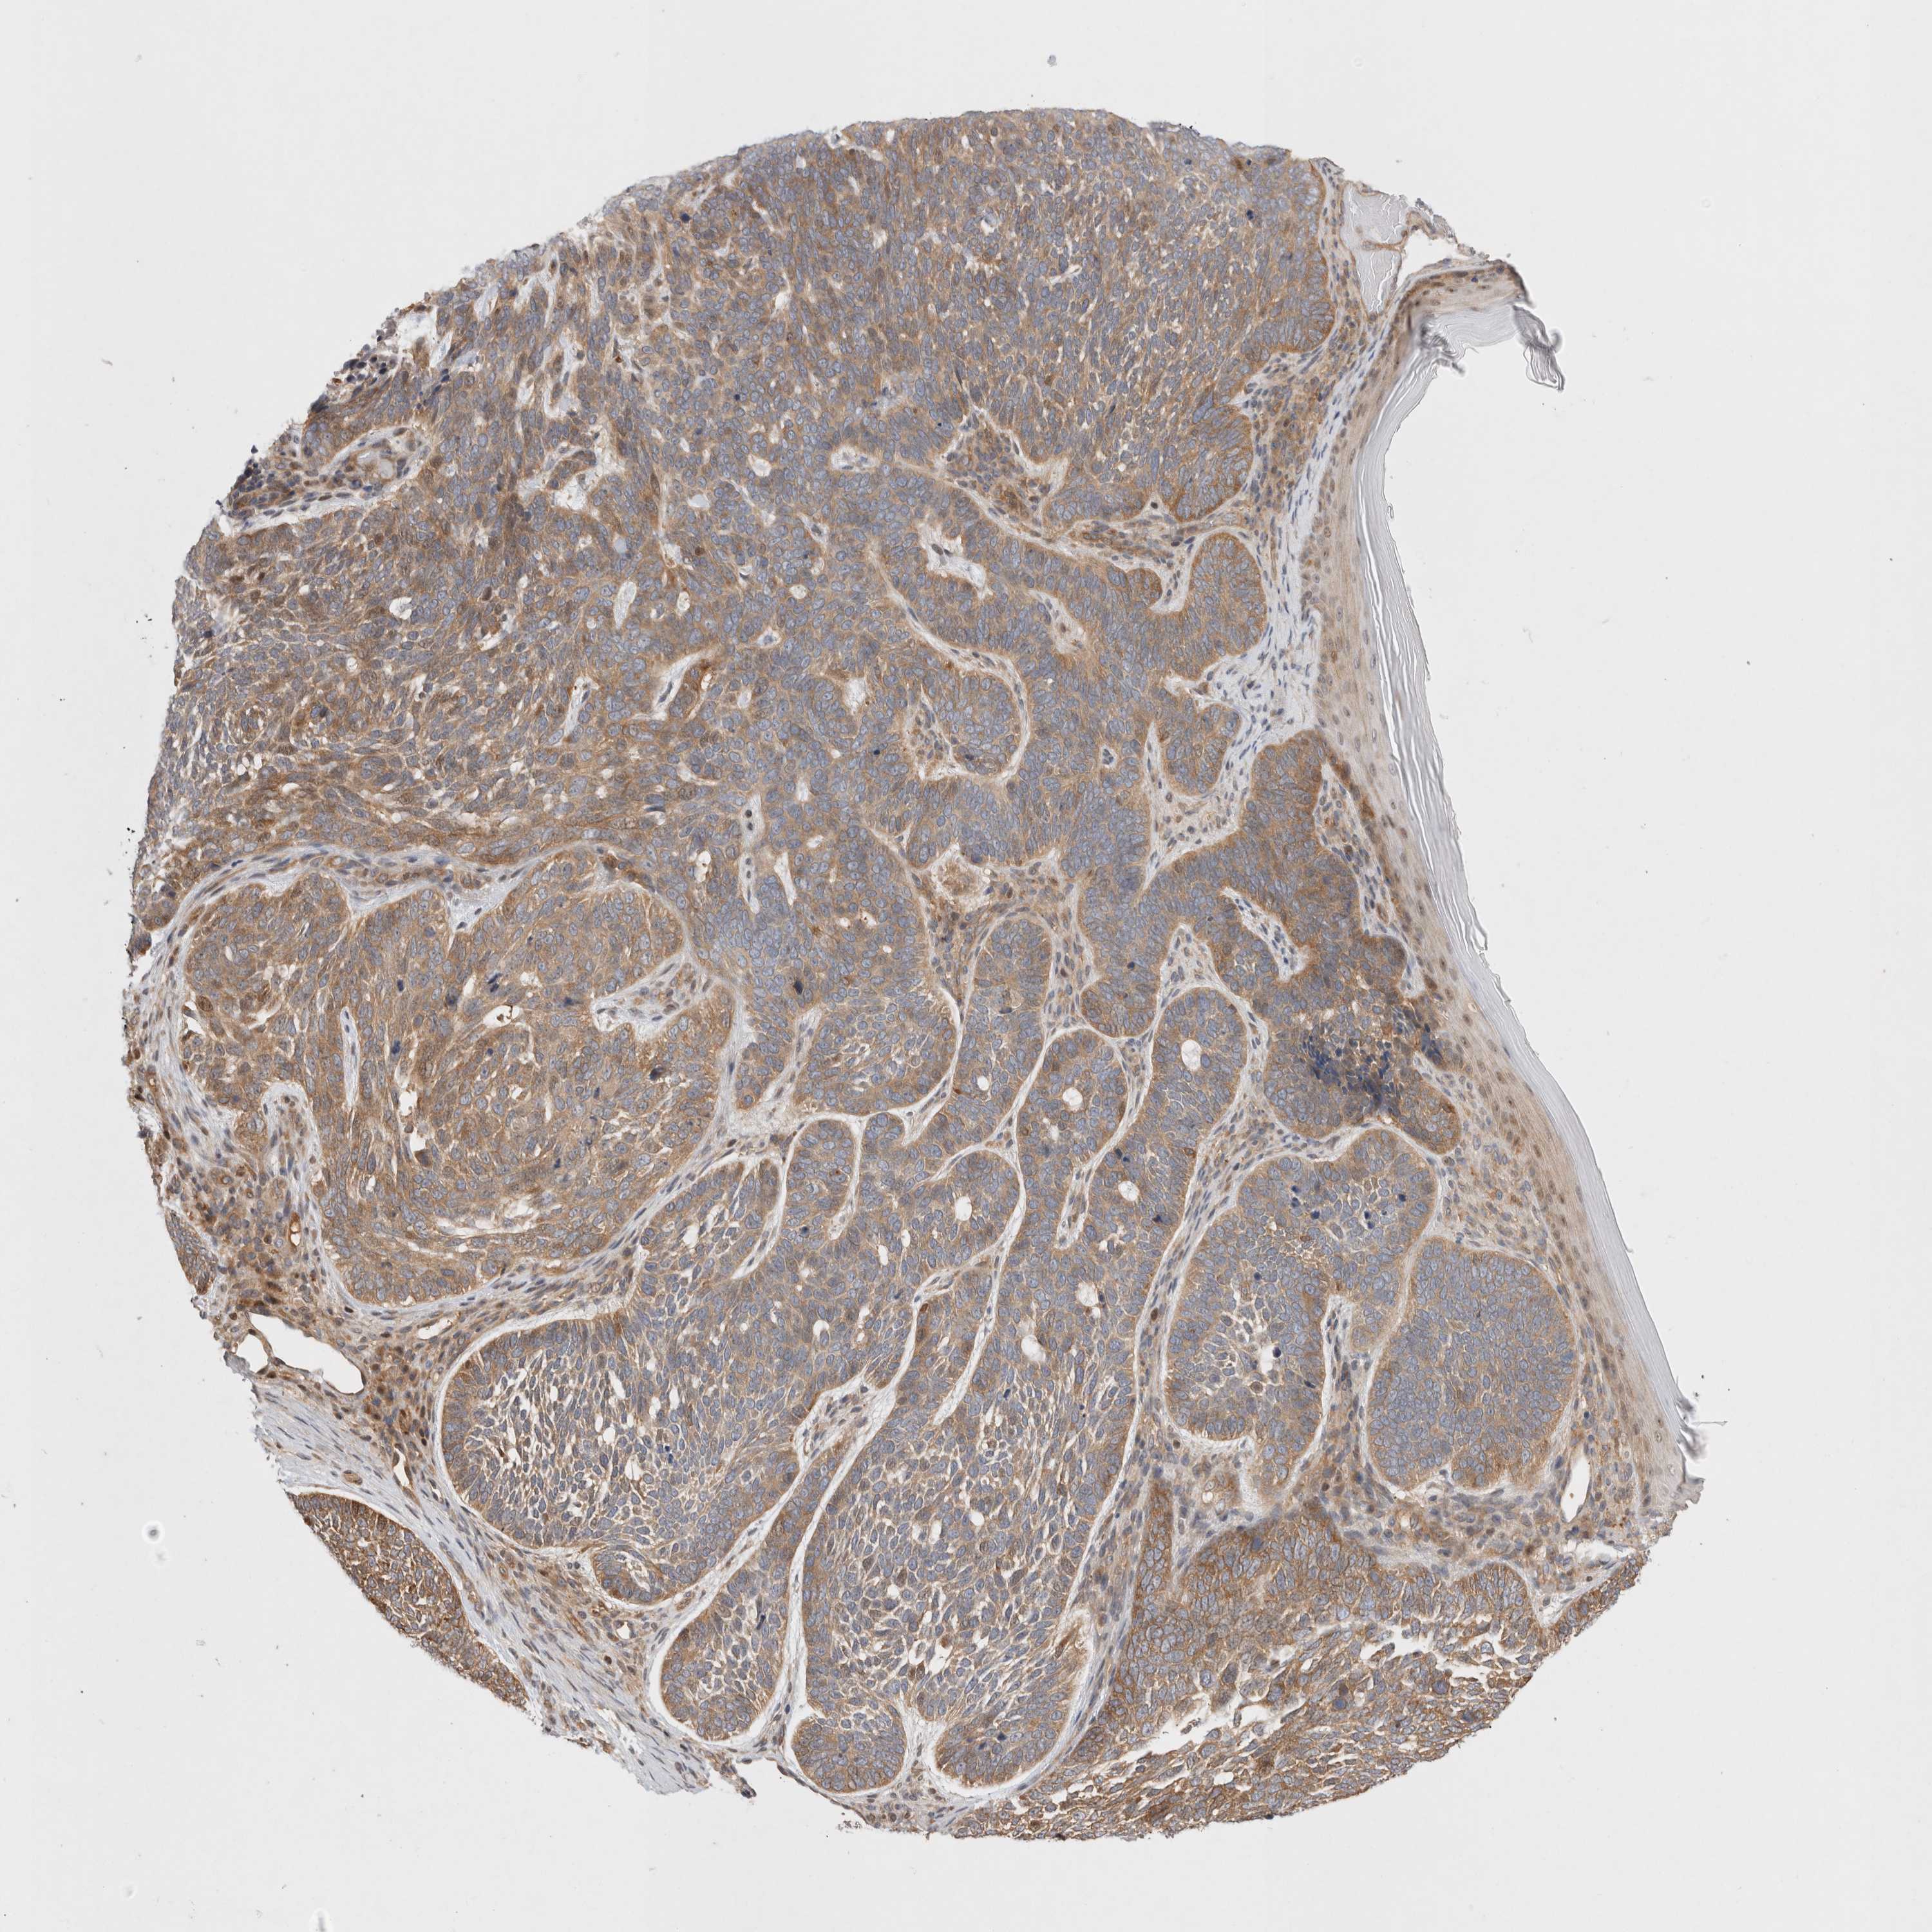

SKIN CANCER - Protein expressioni

A mouse-over function shows sample information and annotation data. Click on an image to view it in a full screen mode. Samples can be filtered based on level of antibody staining by selecting one or several of the following categories: high, medium, low and not detected. The assay and annotation is described here.

Each image is clickable and will lead to virtual microscopy that enables deeper exploration of all samples and also displays staining intensity scores, fraction scores and subcellular localization as well as patient and tissue information for each sample.

Antibody HPA026114

Antibody HPA051524

Antibody CAB002756

Staining

High

Medium

Low

Not detected

Intensity

Strong

Moderate

Weak

Negative

Quantity

>75%

75%-25%

<25%

None

Location

Nuclear

Cytoplasmic/membranous

Cytoplasmic/membranous,nuclear

Basal cell carcinoma

Squamous cell carcinoma, NOS

Squamous cell carcinoma, metastatic, NOS